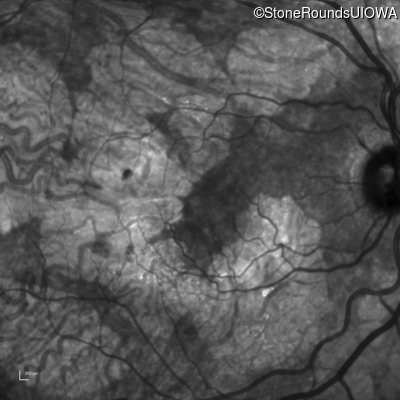

Infrared Fundus Photograph - Right - 20/40 -2 sc

Exemplar

Infrared Fundus Photograph - Left - 20/60 sc